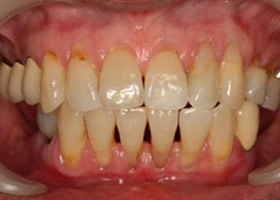

治療前全口x光片、口內照片

術前缺牙無法咀嚼